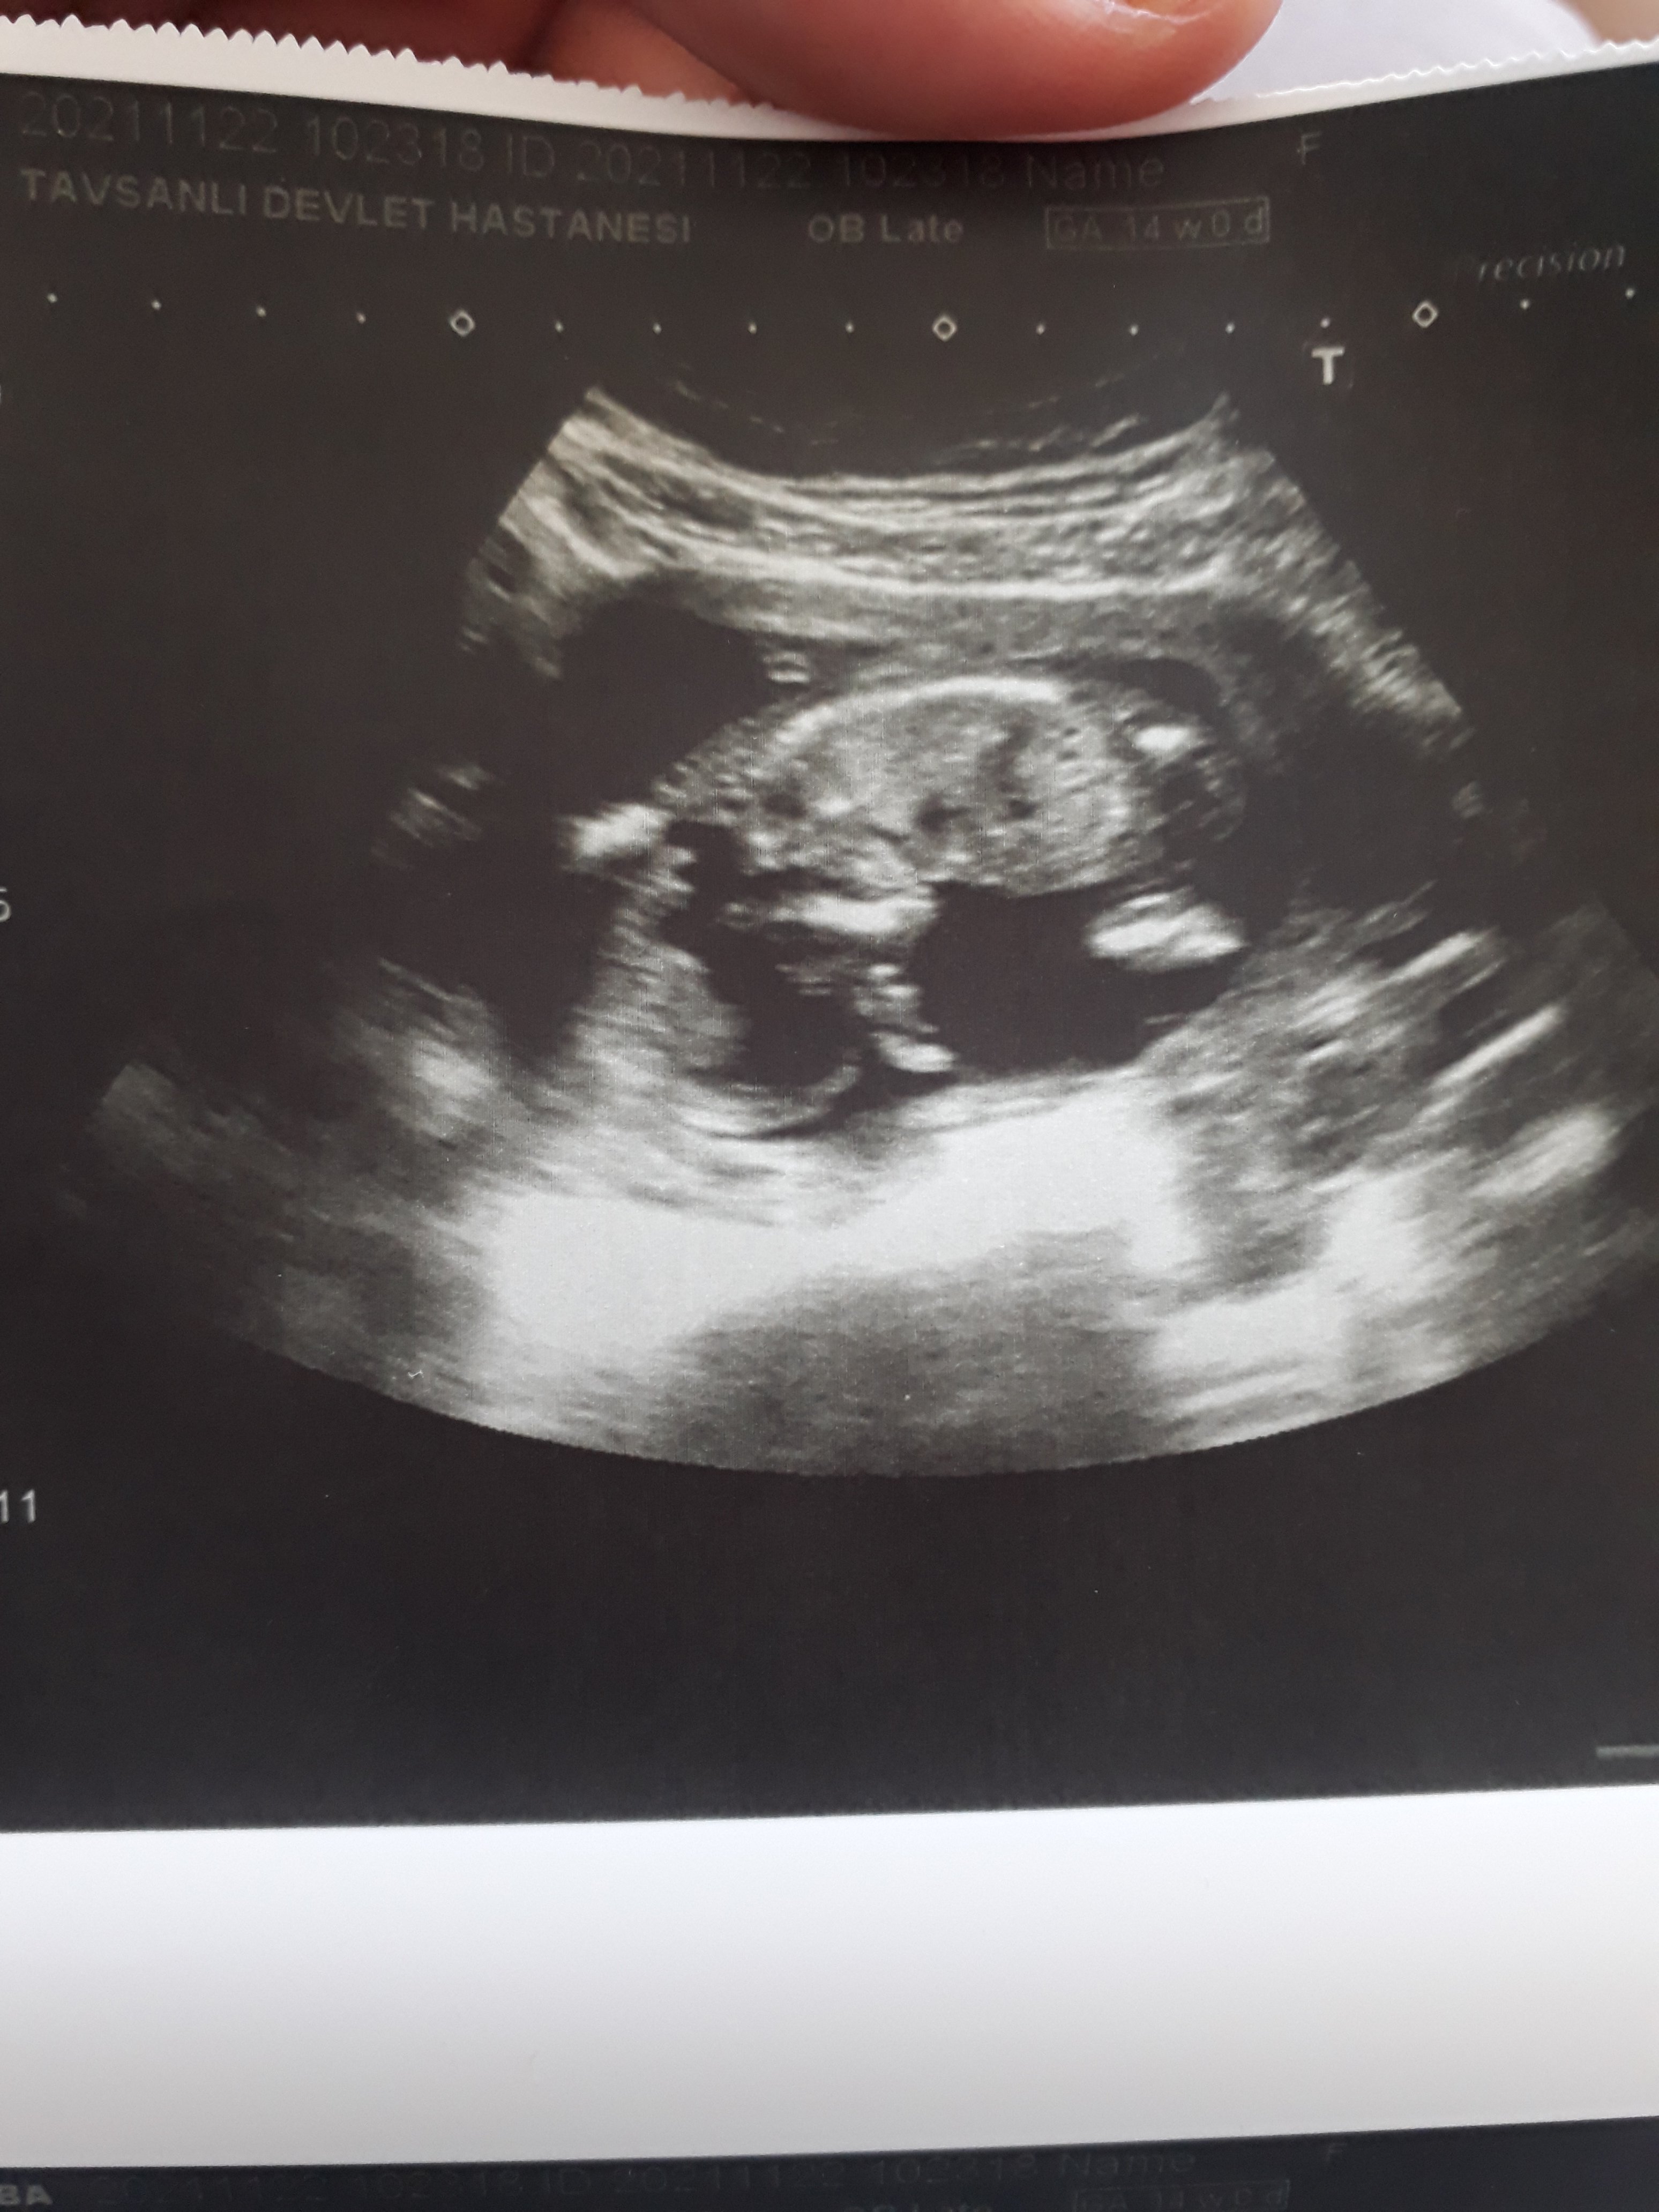

Resme bakarmisniz😊😊cinsiyeti soylemedi doktor

Ins canim banada kiz gibi gelio ya bilmiom dojtora sordum kabarıklık gordum dedi şeyinde😂bende sustum bisiy demedim sonra doktor 15gine daha belli olur dedi 🙃